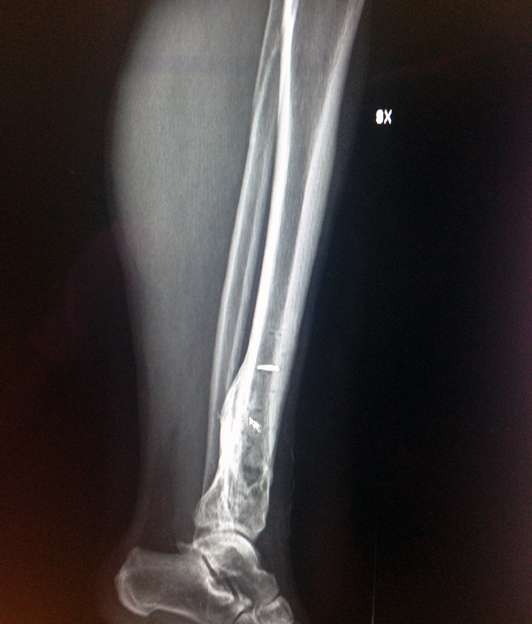

Gambetta lavorata: speriamo sia tutto ok!

Vedevo due cose bianche che mi sembravano chiodi ...

Quello più in alto è un pezzo di punta di trapano rimasta dentro alla seconda operazione, l'altra è la freccia del mouse sul monitor dove ho fatto la foto.